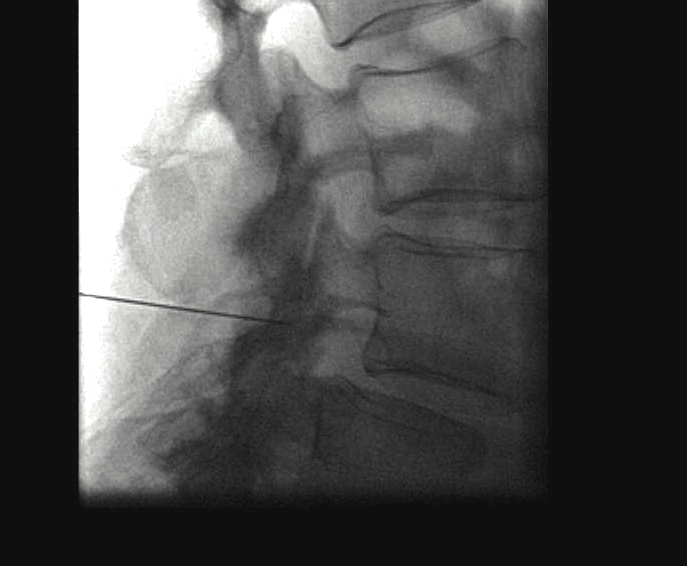

Percutaneous Discectomy

Indications

- contained disc

Technique

- image guidance / endoscopic techniques

- interlaminar or transforaminal

- discectomy with cutting / suction probe

Advantage

- minimal scar

- rapid recovery